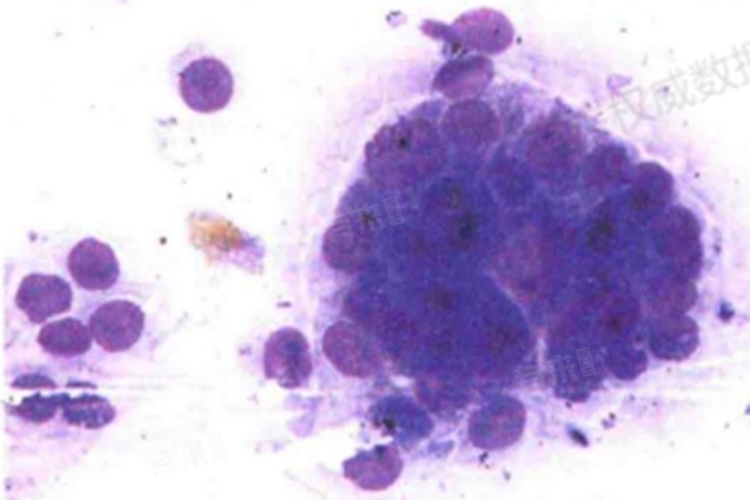

中-低分化腺癌是一种对癌细胞分化程度的描述,它指的是癌细胞在组织学上的分化程度介于中度和低度之间。在组织学上,癌细胞的分化程度反映了其与正常细胞相似度的程度。高度分化的癌细胞与正常细胞相似度较高,而中度和低度分化的癌细胞则表示其分化程度较低,失去了部分或完全正常细胞的特征。

- 具体来说,中-低分化腺癌的特点包括细胞异质性较高,即癌细胞形态、大小、染色质等特征存在较大的差异;生长速度相对较快,这是因为癌细胞失去了正常细胞的生长调控机制,以及对治疗的反应较差,由于癌细胞分化程度低,其对药物或放射线的敏感性也较低,因此治疗难度相对较大。